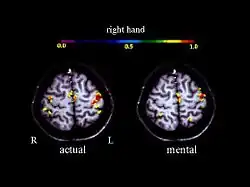

A large number of functional neuroimaging studies have demonstrated that motor imagery is associated with the specific activation of the neural circuits involved in the early stage of motor control (i.e., motor programming). This circuits includes the supplementary motor area, the primary motor cortex, the inferior parietal cortex, the basal ganglia, and the cerebellum.[21][22] Such physiological data gives strong support about common neural mechanisms of imagery and motor preparation.[23]